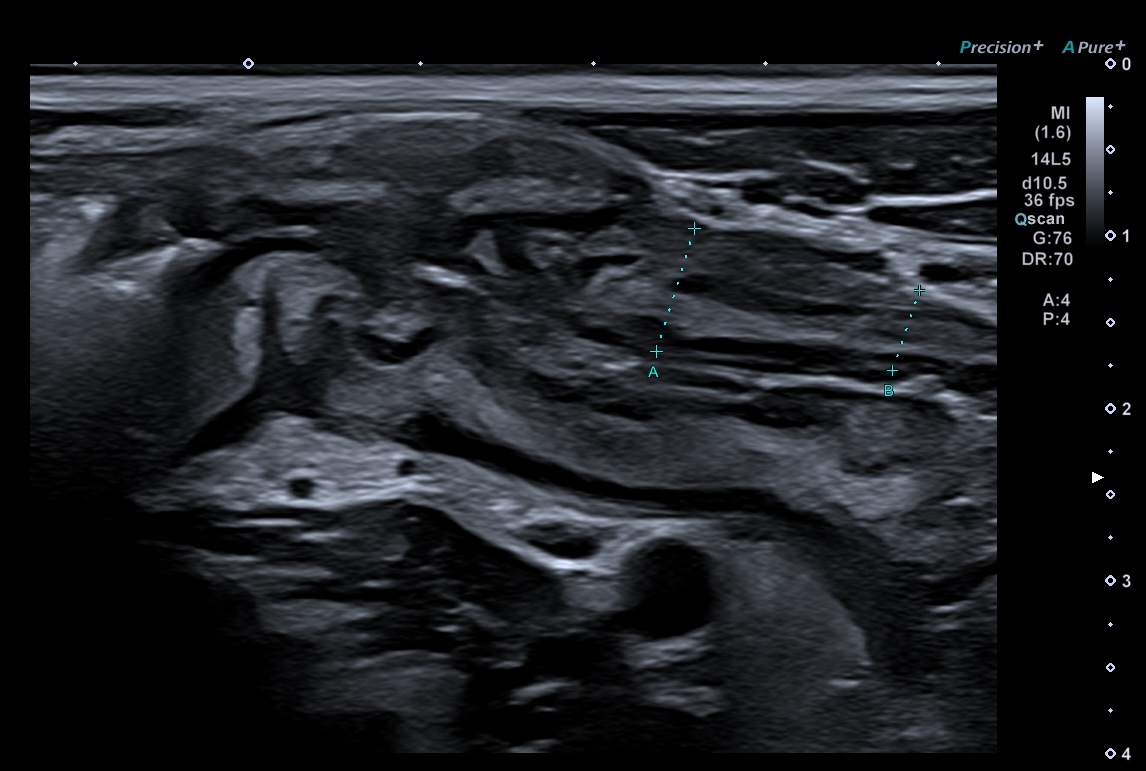

ci-dessous même iléîte terminale vue en basse fréquence et en haute fréquence, iléïte passant devant les vaisseaux iliaques

la sonde HF est la seule qui permette une analyse précise de la paroi